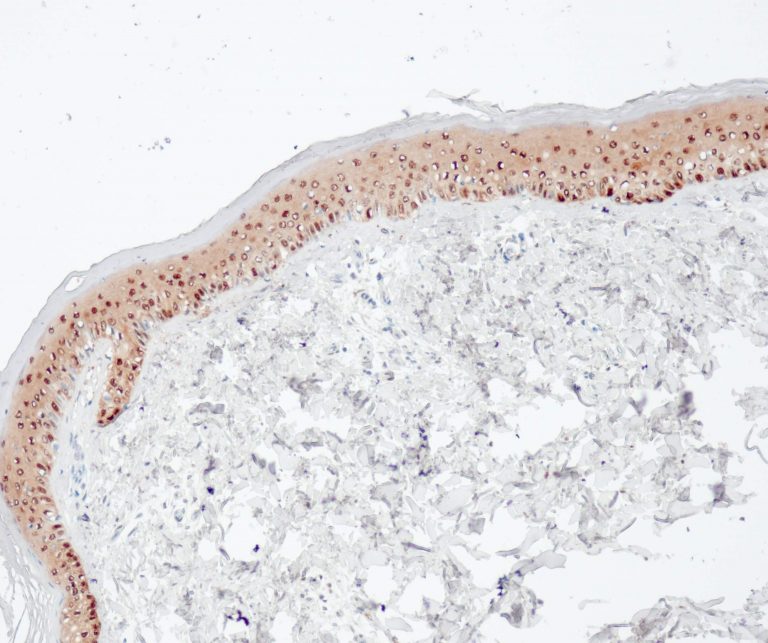

Vascular Pathology

Gastrointestinal (GI) Pathology

General Marker

Breast Pathology

Endocrine Pathology

Gynecological Pathology

Neuropathology

Infection Markers

Lung Pathology

Urinary Tract Pathology

Transplantation Pathology

Soft Tissue Pathology

Hematopathology